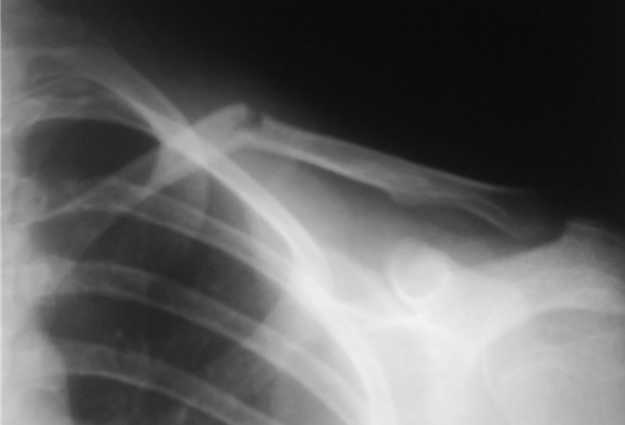

Уважаемые коллеги, травматологи, памятуя о недавней дискуссии о лечении диафизарных переломов ключицы, "Как ключицу не лечи, все равно правильно срастется", поведаю о таком случае.

Девочка 14 лет, на даче упала с турника 05-07-08, в наш травмпункт обратились на следующий день - Диагноз: Закрытый перлом диафиза левой ключицы. Дежурным травматологом наложена 8-образная гипсовая повязка. На следующий день, родители привели девочку с жалобами на давление в левом надплечье и онемение правого предплечья и 1,2, 3-го пальцев кисти.

Мной была немедленно снята наложенная накануне повязка, и заменена на марлевую Дезо. 09-07-го, Дезо заменена на "косыночную" повязку.Сегодня произведен контрольный снимок -На сегодняшний день сохраняется онемение 1-3 пальцев.